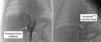

A 1.5-month-old infant was referred for a paediatric cardiology review due to poor weight gain and breathlessness. On examination, he had increased work of breathing and a gallop rhythm. The transthoracic echocardiogram showed dilatation of the left atrium and ventricle, and no intracardiac shunts. Chest computed tomography showed a large aortopulmonary collateral artery originating in the abdominal aorta (Figure 2), irrigating a small portion of the right lower lobe. He underwent transcatheter embolization of the collateral artery (Figure 3) and is now 12 months old and asymptomatic.